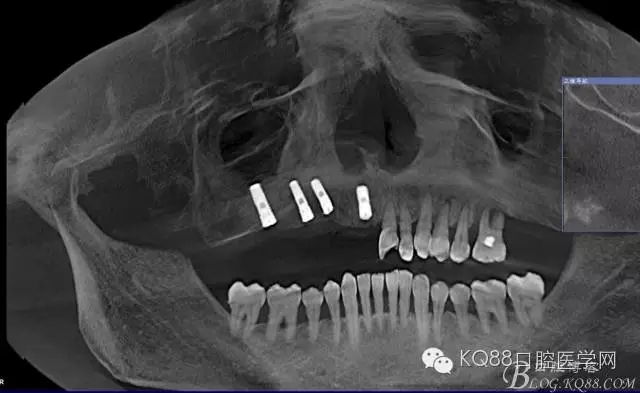

金剛砂球鉆制備橢圓形骨窗,遠中邊緣延伸到上頜結(jié)節(jié),取下骨島,骨角和尖銳的邊緣打磨圓鈍,暴露上頜竇黏膜,分離提升上頜竇黏膜。

定位桿定位,擴孔,備洞,bio-oss骨粉和CGF混合后充填竇腔

植入植體,骨島覆蓋上頜骨側(cè)壁骨窗

bio-guide屏障膜覆蓋側(cè)壁骨窗,牙槽嵴頂缺損部位植骨,嚴(yán)密縫合。